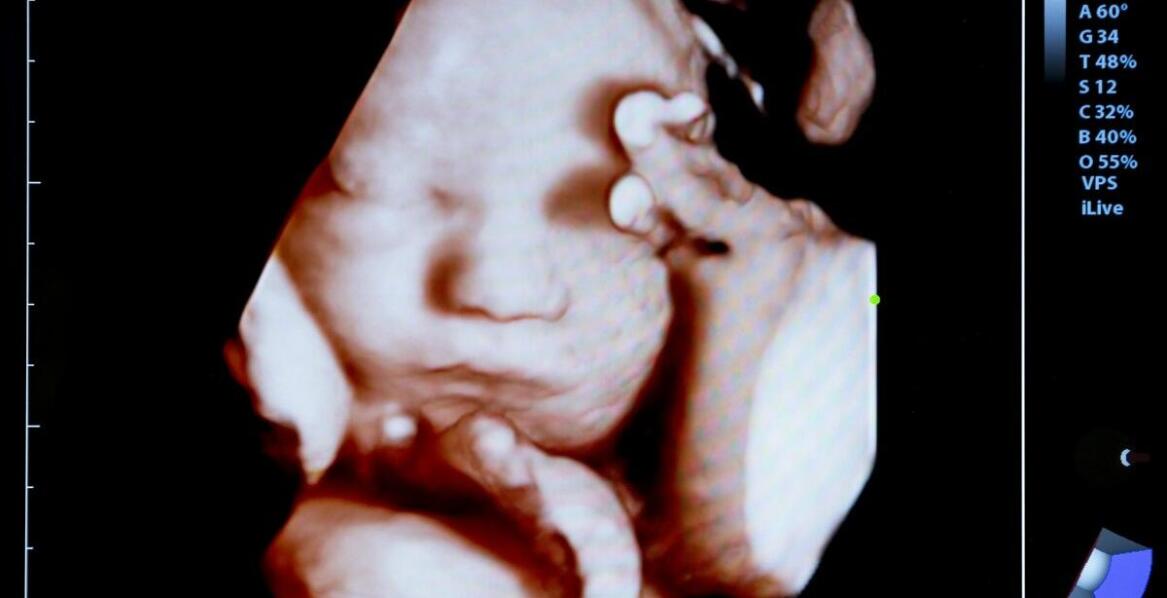

USG główki noworodka – przebieg badania i najważniejsze korzyści diagnostyczne

USG główki noworodka (USG przezciemiączkowe) pozwala szybko ocenić struktury mózgowia u niemowląt bez promieniowania i bez bólu. Badanie trwa zwykle 15–20 minut, nie wymaga specjalnego przygotowania i może być powtarzane. Największą wartością jest wczesne wykrycie nieprawidłowości, takich jak krwawi